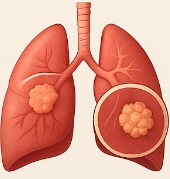

폐암 초기증상의 주요 특징

폐암 초기증상은 일반적인 호흡기 질환과 유사해 구별이 어렵습니다. 하지만 지속 기간과 강도를 통해 구분할 수 있습니다.

- 지속적인 기침: 3주 이상 낫지 않는 기침.

- 호흡곤란: 평소보다 숨이 차는 느낌.

- 혈담: 가래에 피가 섞여 나옴.

- 체중 감소: 원인 없는 급격한 체중 감소.

이런 폐암 초기증상이 반복되거나 악화되면 반드시 검진을 받아야 합니다.